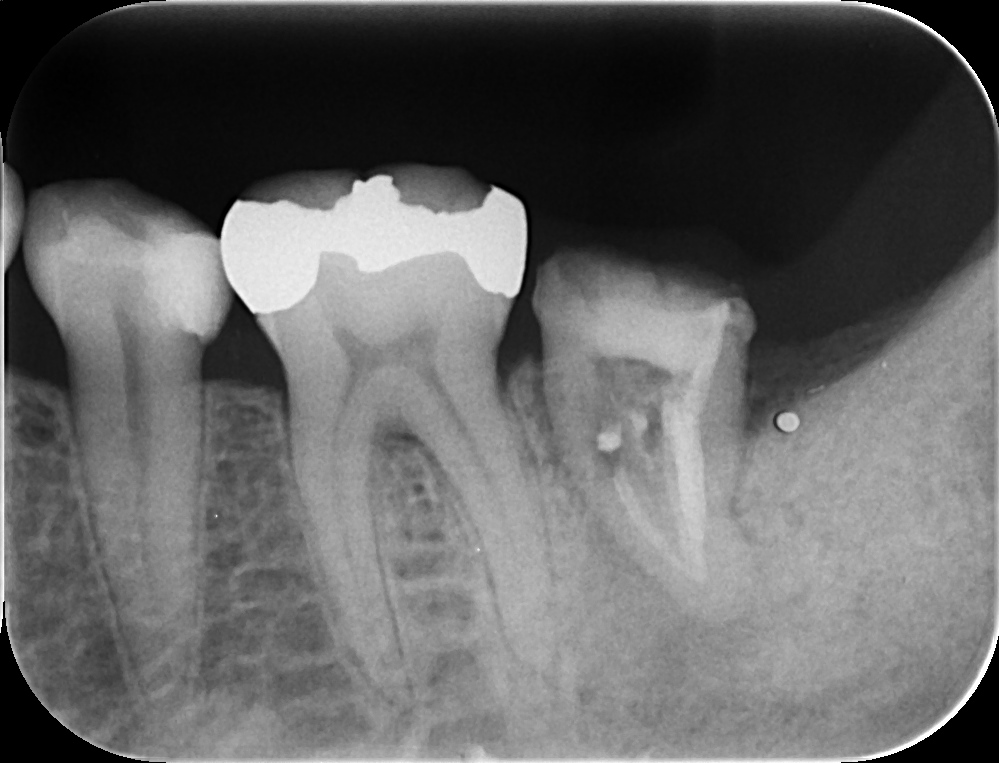

コーヌスデンチャーとは残っている歯に冠のような金属を被せてその上にさらに金属を被せる

2重の冠でできた入れ歯になります。茶筒の原理で固定されるため安定感が高く、審美性や装着感に

優れています。ドイツで開発されたテレスコープデンチャーの一種です。